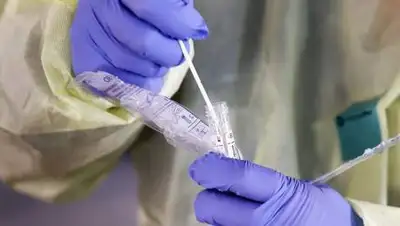

Istock

Istock